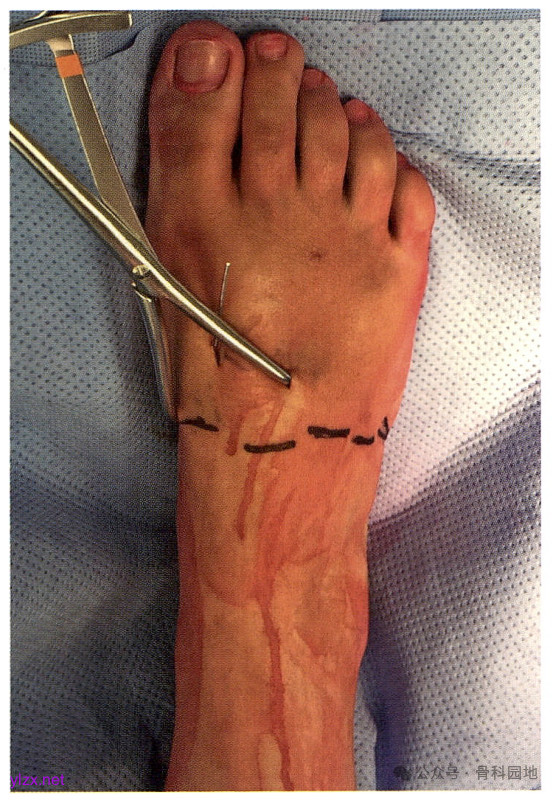

体位:Lisfranc 损伤经皮固定的经典手术体位。本例为左足损伤。在同侧髋部下方垫高,将患足位置调整合适。

大多数损伤的第2MT都是向外半脱位的。将第2MT基底复位到第1MT基底外侧和内侧楔骨外侧关节面形成的凹陷中。在内侧楔骨的内侧皮质和第 2 MT基底外侧经皮放置一个中号复位钳,然后钳夹复位。